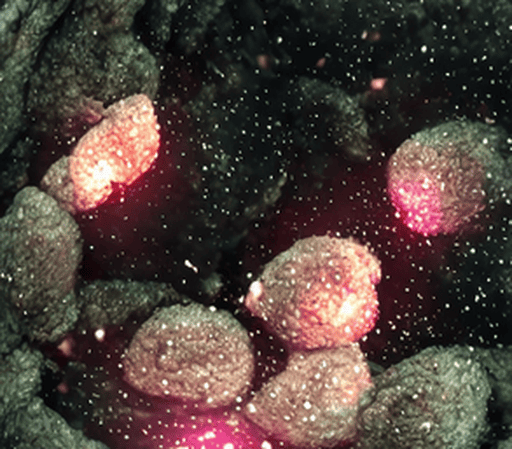

At the organ level, editing difficulty varies significantly. Regions such as the spine and bones (e.g., CT scans) remain especially challenging, with the best EA only reaching 0.38. This difficulty is not primarily due to grayscale input but rather the inherent structural complexity of bones. Unlike soft tissues, bones follow rigid, geometrically consistent patterns (e.g., aligned vertebrae, symmetric ribs), making even small editing errors visually salient and disruptive. For example, in a task like “correct spines”, the model must straighten the spine without disturbing rib symmetry or vertebral alignment, demanding a much higher degree of structural precision than tasks such as “remove intestinal polyps”. The largest performance gaps between Gemini and open-source models are seen in teeth (34%), hands (64%), and gastrointestinal tract (43%), further reflecting the challenges posed by complex anatomical structures and repetitive patterns. Conversely, superficial structures such as hair and nose are easier to edit, where ICEdit achieves strong performance (hair: EA = 0.71, VQ = 0.79).

Three key observations arise: (1) Internal organs are significantly harder to edit than superficial structures, with EA scores averaging 2.3 lower; (2) Gemini’s advantage is most pronounced in anatomically complex regions with repetitive patterns (e.g., hands, gastrointestinal tract); and (3) A trade-off exists between visual quality and context preservation: models with higher VQ, such as Gemini, tend to exhibit slightly lower CP, highlighting the need for localized, precise edits rather than full-image redraws in medical applications.

| Previous | Truth | Gemini2 | SeedX | Imagic | IP2P | InstructDiff. | PaintByInpaint | ICEdit |

| Remove the diminutive polyp. | 0.8/0.8/0.9 | 0.1/1.0/1.0 | 0.9/0.9/0.9 | 0.6/0.7/1.0 | 0.0/0.3/0.9 | 0.2/0.2/0.8 | 0.9/0.9/1.0 | |

| Remove intestinal polyps. | 0.8/0.8/0.8 | 0.2/0.3/0.2 | 0.2/0.7/0.5 | 0.3/0.7/0.8 | 0.1/0.5/0.7 | 0.0/0.3/0.3 | 0.2/0.6/0.7 | |

| Remove intestinal adenoma. | 0.8/0.6/0.9 | 0.7/0.7/0.7 | 0.2/0.5/0.3 | 0.0/0.6/0.8 | 0.0/0.3/0.2 | 0.0/0.4/0.5 | 0.0/1.0/0.9 | |